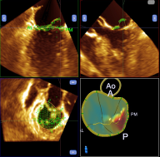

この治療法では、特に3Dエコーが有用性が高く、治療の際に役立っています。術中の例として、図のように、心房中隔の卵円窩を同定し、安全に左房内へカテーテルを誘導する手助けをしています。

僧帽弁解析(mitral valve quantification:MVQ)

僧帽弁の幅や高さ、前尖と後尖のバランスなどを数値化して評価することが可能となります。僧帽弁のgeometry(形態)を主観的な評価のみでなく、客観的な評価も行います。人工弁輪の適正なサイズ選択を事前に推定することにより、人工心肺時間や手術時間の短縮に貢献します。